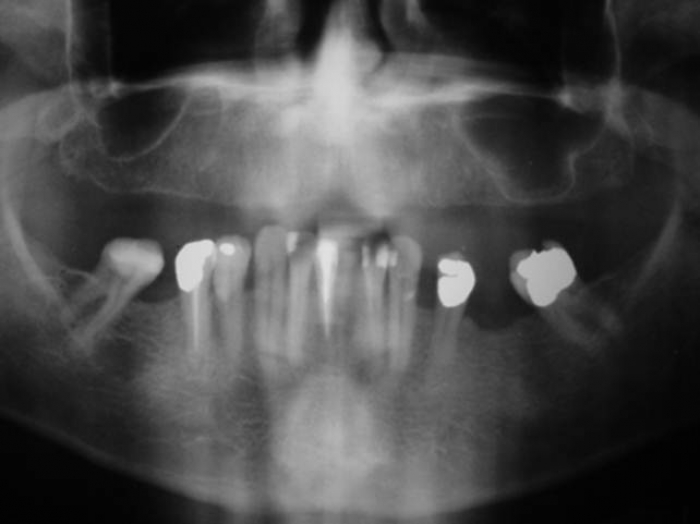

Raio X inicial

Imagem após enxerto ósseo na maxila